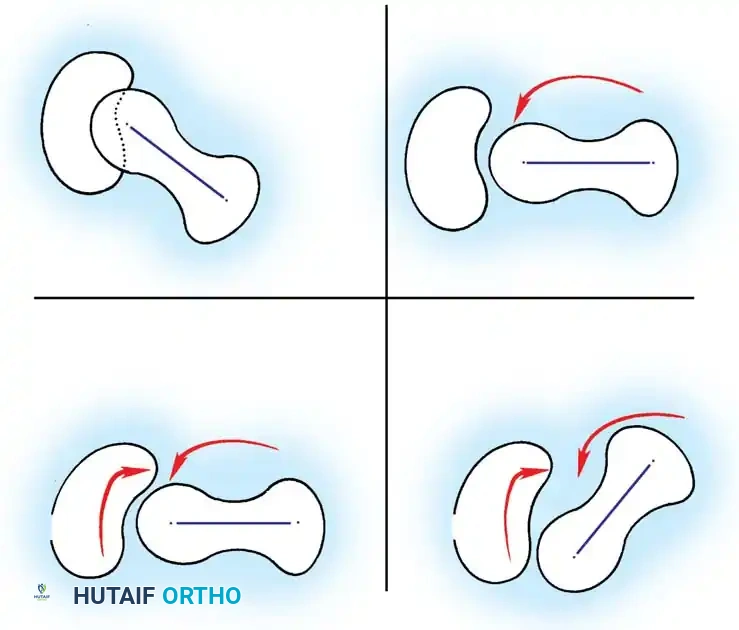

Routine clinical screening must include the Ortolani test and the provocative maneuver of Barlow.

* Ortolani Maneuver: Performed by gently abducting and elevating the flexed hip to detect the reduction of a dislocated femoral head into the true acetabulum. A palpable "clunk" indicates a positive test.

* Barlow Maneuver: Detects potential subluxation or posterior dislocation by applying direct posterior pressure on the longitudinal axis of the femur while the hip is in adduction.

Fig 27-1: Ortolani maneuver for routine screening. The examiner stabilizes the pelvis, places the index and middle fingers over the greater trochanter, and gently abducts the hip.

Surgical Warning: Both tests require a relaxed, pacified child. Forceful maneuvers must be strictly avoided, as they can damage the delicate infantile articular cartilage or cause iatrogenic instability.